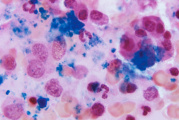

Na povrchu kostí se nachází hutná kostní tkáň (a), uvnitř nich je tkáň houbovitá (spongiózní, b). Houbovitou tkáň a dutiny v dlouhých kostech vyplňuje kostní dřeň (c). V ní vznikají krevní tělíska (např. červené krvinky). Aby se tyto součásti krve dostávaly na místo určení a aby kosti získávaly výživu, zasahují do nich cévy (d).